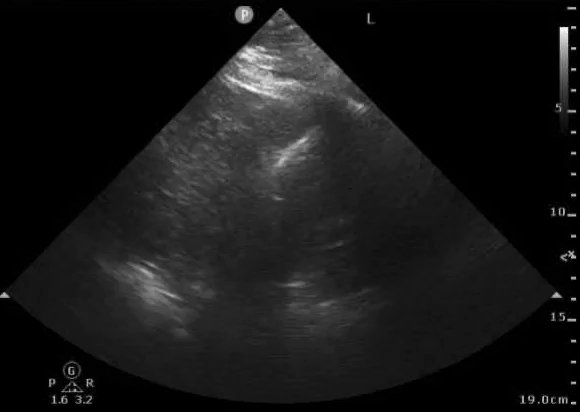

Right side, for comparison.

9/